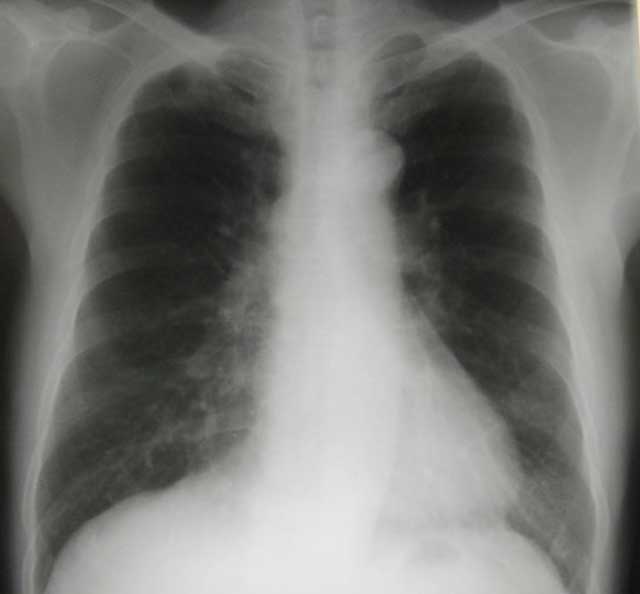

1. Henry was then 50 years old. Sometime in September 2003, he started to have persistent coughs. Antibiotics did not help him. An X-ray, done in November 2003, showed presence of a 1.5 cm lump in his left lung.

A CT scan indicated a mass in the right upper lobe of the lung. There were also several smaller satellite lesions adjuvant to the mass. No calcification or cavitation was noted within the mass. There was no mediastinal lymphadenopathy. Two rounded hypodense lesions were noted in Segment 4 and 7 of his liver. The larger was in Segment 4 which was 1 cm in diameter. A cortical cyst was noted in the left kidney. Impression: cancer of the lung. The hypodense lesions in the liver could represent either cysts or metastases.